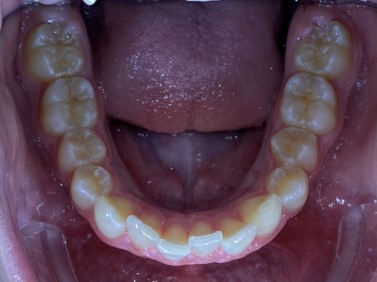

Chief complaint: We present the case of a 12-year-old female patient who came for an orthodontic evaluation, motivated by a family history of treatment. Clinical and radiographic analysis revealed a skeletal Class II malocclusion with molar and canine relationships also in Class II, moderate crowding in both arches, a deviation of the dental midline, and ectopic eruption of tooth 13. No functional issues with breathing or swallowing were observed, and oral health was generally good. A slight mandibular retrusion was noted in the soft tissue profile. A treatment plan was proposed using the Angel Aligner Pro system, aiming to correct dental misalignments and improve facial harmony through a minimally invasive, growth-adapted approach.

- Moderate upper and lower crowding

In the upper arch, the main goal will be to correct the Class II malocclusion by distalizing the upper posterior teeth in order to resolve crowding without proinclining the incisors. This movement will be accompanied by an asymmetric “bite jump” of 1 mm, which will help improve the skeletal Class II discrepancy, promoting mandibular projection, especially considering that the patient is still in the growth phase. Additionally, bilateral and symmetric expansion will be planned until a torque of 0° is achieved, allowing for proper transverse alignment and greater stability of the final result. Lingual button cutouts will be placed on teeth 14 and 24 to facilitate the required movements. To optimize control and retention, vertical mesial beveled attachments, as large as possible, will be placed on the premolars and molars, as well as on teeth 12 and 22, reinforcing the mechanics in the anterior sector. The inclination of the central incisors 11 and 21 will be corrected according to the visual reference provided in the clinical image. Furthermore, it will be necessary to center the upper midline by shifting it 0.5 mm to the left to achieve greater aesthetic symmetry. As for the lower arch, treatment will begin with a phase of expansion and derotation of the posterior teeth, which will set the stage for subsequent movements in the anterior sector. Once this goal is achieved, alignment of the teeth from canine to canine will proceed, aiming to minimize anterior interproximal reduction (IPR) and avoid unnecessary round- tripping movements of the incisors. Vestibular button cutouts will be made on teeth 36 and 46, while teeth 37 and 47 will have horizontal attachments that will serve as anchorage to ensure stability during treatment.